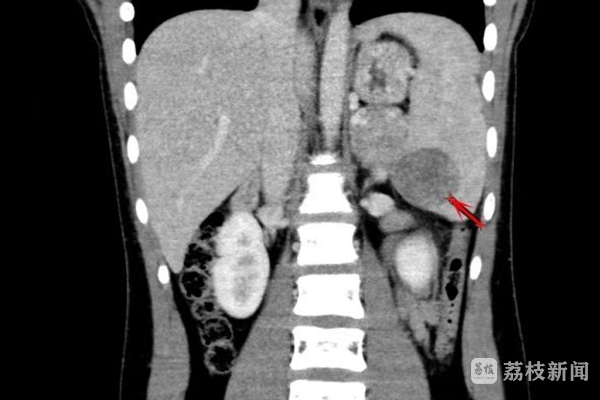

在该院普外科门诊就诊后,珊珊被收入病房。普外科主任姜斌表示:“从腹部CT可见,患儿脾脏有一处肿瘤,虽然良性的可能性很大,但因为无法明确性质,仍需要尽快手术切除。”得知珊珊的病情,父母向医生表达了担忧,“手术的风险是不是很大?脾脏切除后对孩子的生长发育有没有影响?”随后,姜斌主任的话缓解了他们的焦虑。“我们采用的是非常成熟的腹腔镜微创手术,将在完全切除肿瘤的前提下,尽可能多保留一部分脾脏组织。”

近日,姜主任带领普外科黄磊主任医师与手术麻醉科合作进行了脾脏肿瘤切除。医生在珊珊的腹部“打了”3个小洞,通过腹腔镜找到脾脏肿瘤的具体位置。由于脾脏含有大量血窦,充满血液,被称为“人体血库”。肿瘤切除前,医生对瘤体周围的脾血管进行了精细分离,并一支一支做了结扎处理,以减少术中出血。手术还运用了3D高清成像技术,为肿瘤定位和精准切除提供了保证。最终,肿瘤顺利切除,术中出血仅10毫升左右,并保留了大约60%的脾脏组织。